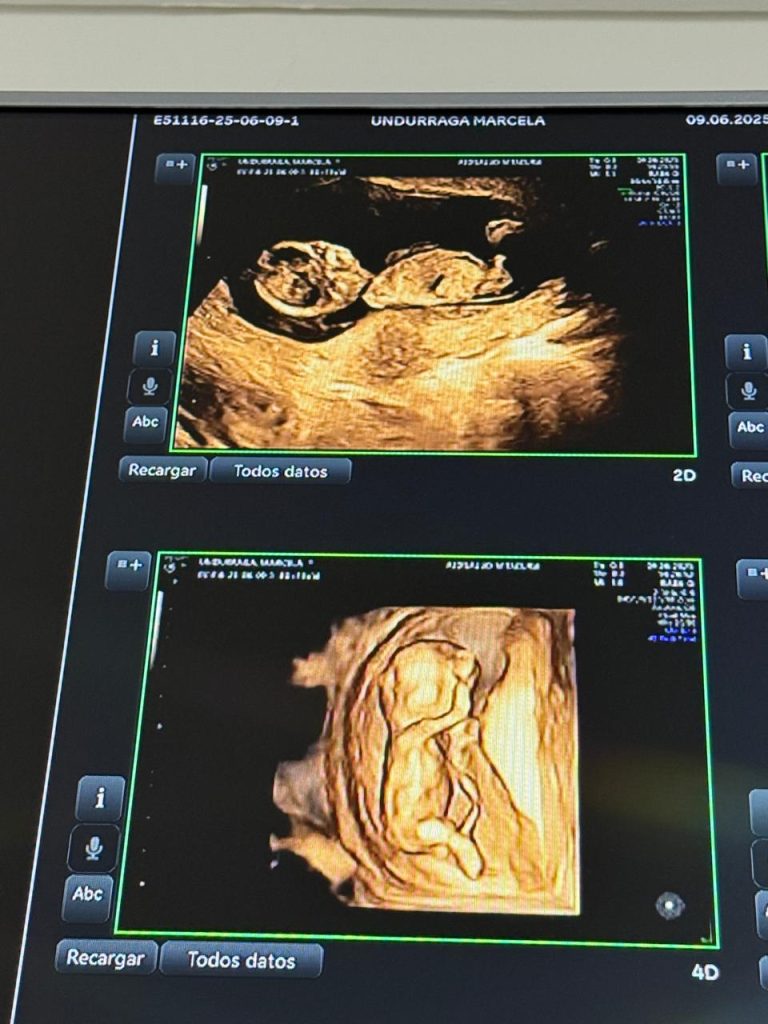

Marcela Undurraga espera a su primer hijo a los 41 años. Dice que tiene miedo. No a perder el embarazo de alto riesgo que está viviendo. Tampoco a que su hijo herede el raquitismo hipofosfatémico, la enfermedad genética con la que convive desde niña y que le ha dejado con: baja estatura, deformidades musculoesqueléticas, náuseas, fatiga crónica, dolores musculares y articulares, además de baja presión y problemas asociados como déficit atencional. Su temor es otro: que nazca con una discapacidad cognitiva.

Nunca imaginó que sería madre y menos a esta edad. El verano anterior lo pasó entre conciertos, cumpleaños y eventos, tomando, fumando y comiendo chatarra. Luego comenzaron los malestares: dolores corporales, mareos y una fatiga persistente que atribuyó a su enfermedad. El año anterior había sufrido una descompensación propia de su condición, así que no le dio mayor importancia. Pero la duda creció. Compró un par de test de embarazo. Todos dieron positivo.

Los médicos consideran que, pasados los 35 años, un embarazo se clasifica como de alto riesgo. El doctor Cristián Jesam, especialista en fertilidad de la Clínica SGFertility, explica a V240 que estos embarazos suelen traer complicaciones como “síndromes hipertensivos del embarazo, diabetes gestacional, parto prematuro y todo lo que significa esto. También la mortalidad de las mamás y de los niños se dispara abruptamente después de los 50 años, por ejemplo”.

Marcela Undurraga reconoce esos riesgos. Los casos que conoce de embarazos posteriores a la edad considerada fértil terminaron con hijos que nacieron con alguna discapacidad cognitiva o con síndrome de Down. Por eso, desde mayo ha estado bajo un seguimiento constante. “No tengo miedo de que haya pérdida, siento que estoy preparada para eso. De hecho, no he comprado nada para la guagua (…). Todo puede pasar”, señala.

Tras los controles con el ginecólogo, le aseguraron que todo iba bien. Había posibilidades de algún síndrome similar al de ella, pero, según Marcela, no es un problema. “Yo sé lidiar con eso y le enseñaría herramientas para poder vivir como una persona útil a la sociedad y una persona normal”, asegura.